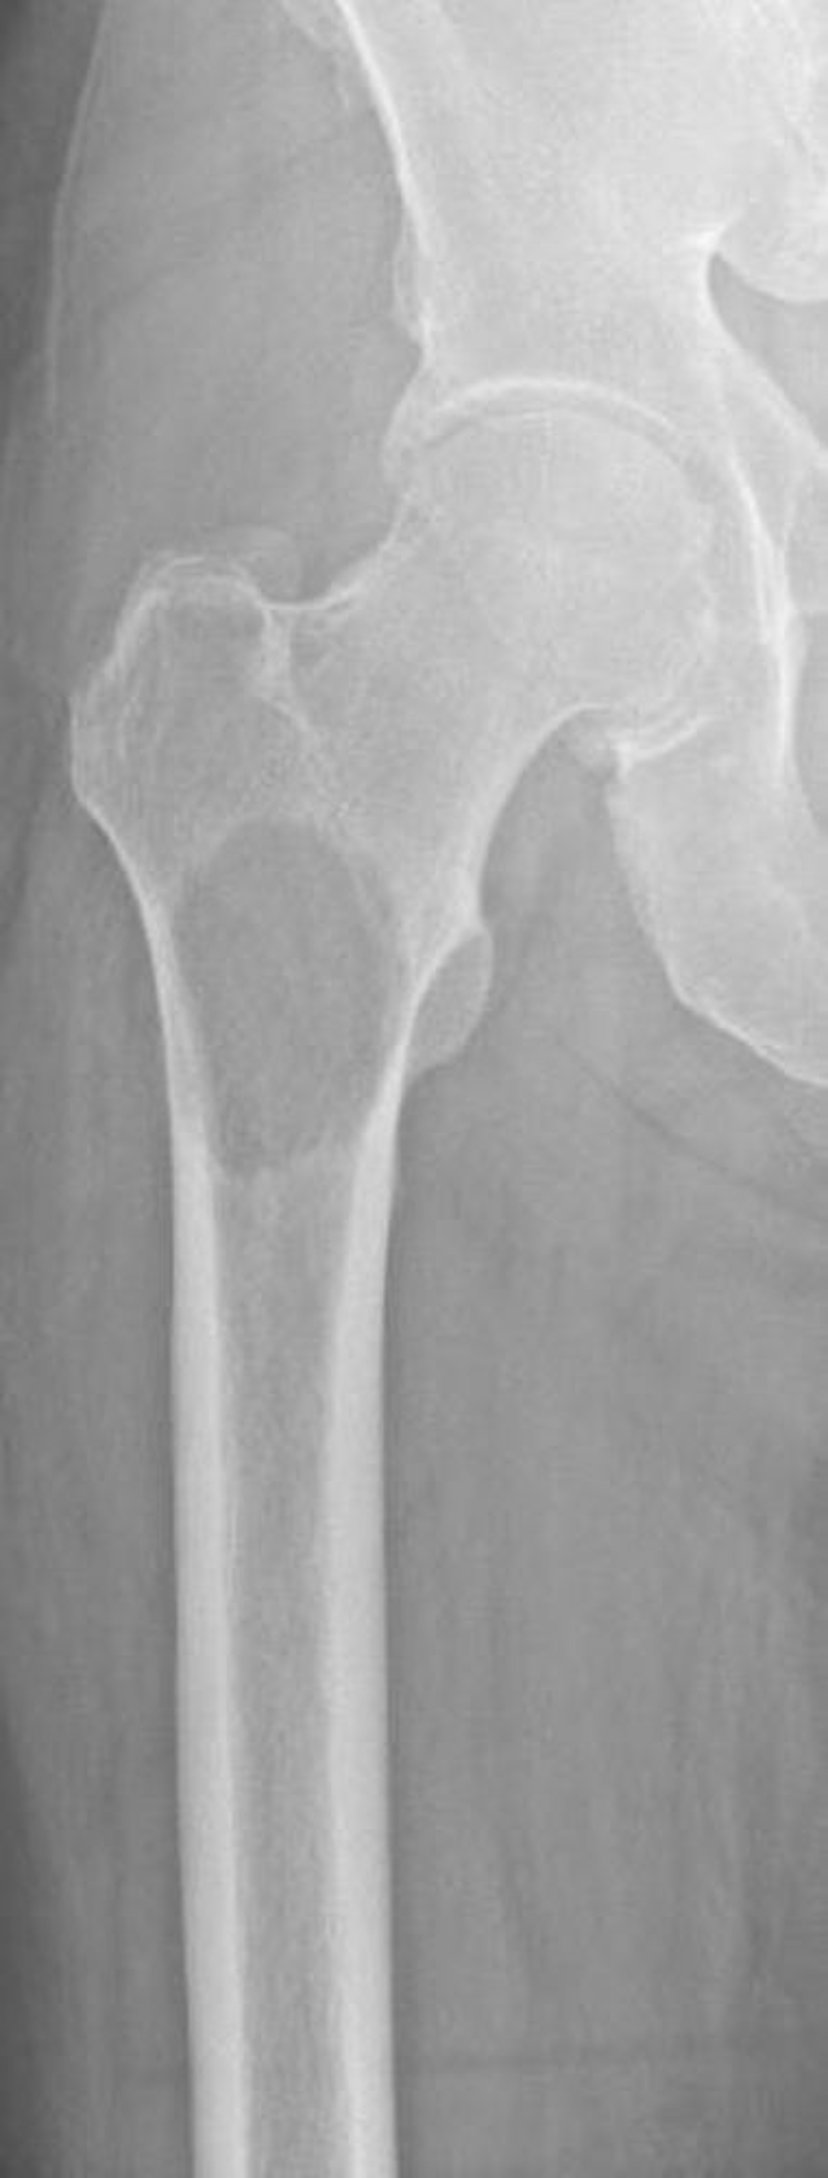

Літичний метастаз проксимального відділу стегнової кістки

This image shows bone destruction due to a metastasis secondary to renal cell carcinoma in the proximal femur. The location and extent of bone destruction make the risk of fracture extremely high (impending fracture).

Image courtesy of Michael J. Joyce, MD, and David M. Joyce, MD.